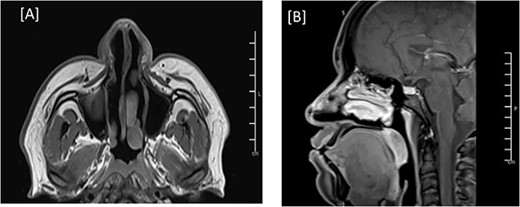

During the physical examination, there was a large globular swelling on the dorsum of the nose extending to both sides with erythema but without warmth (Fig. 1). The patient’s breathing was not affected. A magnetic resonance imaging (MRI) of the head with contrast showed a multiloculated midline cystic lesion on the dorsum of the nose, with some parts showing high proteinaceous content. No connection to the cranial cavity was observed (Fig. 2). These features suggest a dermoid cyst. The size of the lesion is depicted in Supplementary Fig. S1.

MRI of the head, and paranasal sinuses (Pre-Op). (A) There is a lobulated multilocular cystic lesion seen at the dorsum of the nose, some of the cysts are showing bright signal intensity in T1 (arrow) and T2/FLAIR (C) (arrow) representing high proteinaceous content. No connection to the cranial cavity, features are likely presenting dermoid cyst. (B) The lesion shows peripheral postcontrast enhancement. No diffusion restriction.